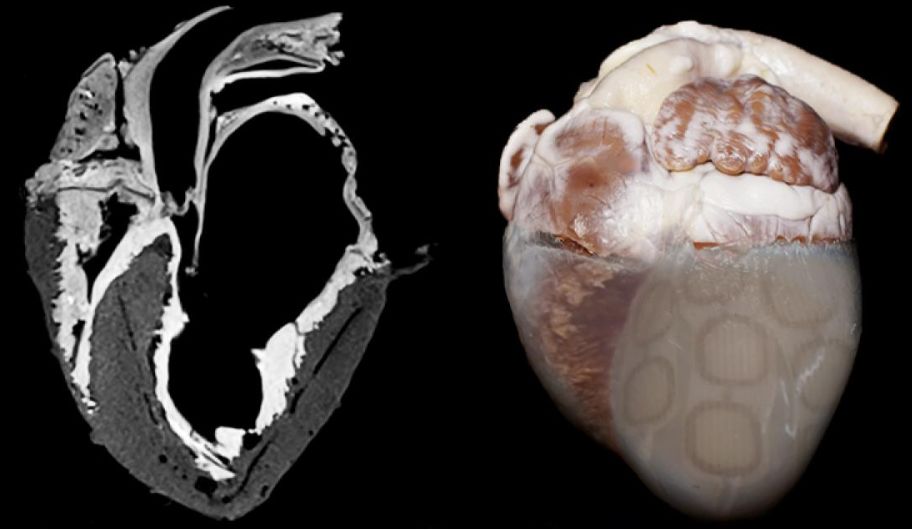

▲图 | “生物机械混合心脏”(来源:AAAS)

这种被称为 “生物机械混合心脏” 的仿生心脏极其接近真实生物心脏,它的构成一部分是用化学方法保存的活体心脏组织,另一部分是帮助心脏输送血液的人造基体。

如下图所示,心脏下部的肌肉组织被替换成了人造心肌,这种人造心肌是一个柔软的、由 TissueSil 粘合剂组合起来的人造模型,类似汽泡纸。

人造肌肉的方向模拟心脏天然的纤维形态,研究人员可以远程充气,通过挤压心脏内部来模拟真实的心脏跳动方式和血液循环。